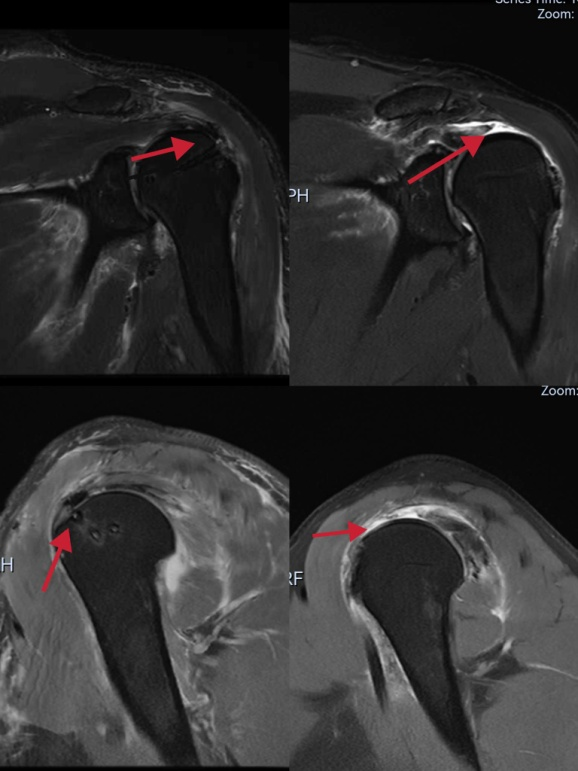

近日,45岁的王大姐(化名)因为肩膀疼痛活动受限到我院骨一科就诊,经了解,王大姐一个月前不慎摔伤,观察了一段时间后肩膀越来越难以活动,经检查,医生惊讶的发现王大姐的肩关节呈假性瘫痪,肩外展,上举、外旋,内旋均无力,MR显示肩袖组织组成的4条肌腱(冈上肌、冈下肌,肩胛下肌,小圆肌)中有3条几乎完全撕裂,肱二头肌腱部分撕裂。

术后与术前的MR对比

因病情严重,骨一科对王大姐的病情进行了详细的研究,迅速制定手术方案,由我院骨一科名医工作室的滕学仁主任亲自主刀,经过手术医生和麻醉师近3小时的努力奋战,在全身麻醉下进行了肩关节镜巨大肩袖撕裂修补术,将撕裂的肩袖完全缝合。与传统手术相比,这种微创手术安全性高、出血少、对组织损伤小、并发症少、恢复快和术后痛苦少,术后王大姐肩关节功能恢复良好。